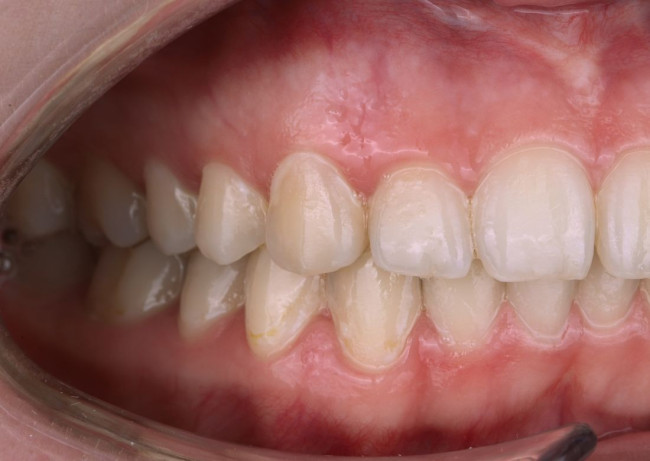

Колоссальный опыт стоматологов — визитная карточка клиники «Виртуоз» в Воронеже. Специально для вас мы создали страничку,

на которой разместили портфолио с работами наших врачей.

Мы регулярно добавляем фото до и после лечения, чтобы вы могли посмотреть финальный результат работы и оценить качество.